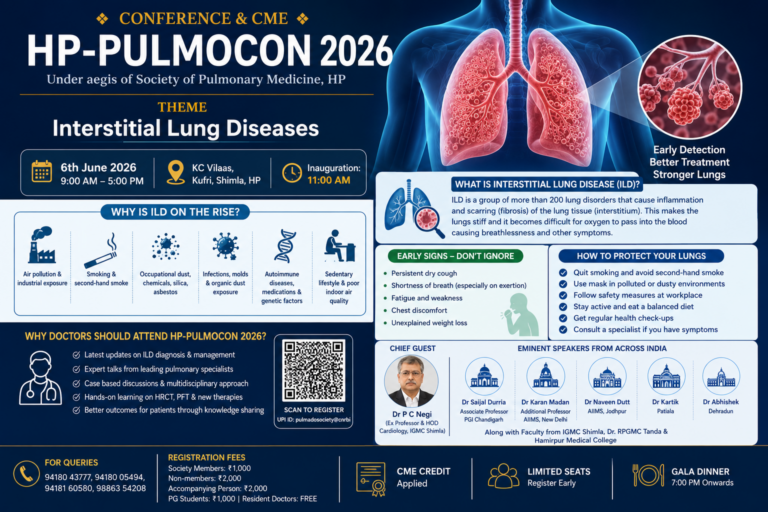

EMHIMACHAL पर आधारित रेस्पिरेट्री डीजीज इमरजेंसी को कैसे ग्रास रूट स्तर पर मशीनों के अभाव के बावजूद...

EMHIMACHAL पर आधारित रेस्पिरेट्री डीजीज इमरजेंसी को कैसे ग्रास रूट स्तर पर मशीनों के अभाव के बावजूद...